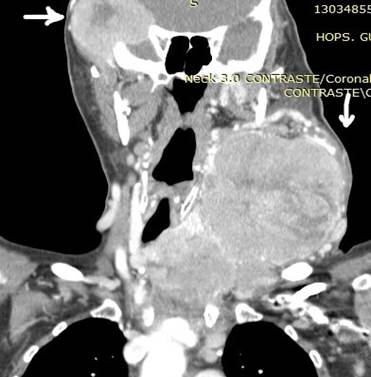

Ilustración 3 TAC: Ca. tiroides vultuoso y metástasis orbitaria

Fuente: Hospital de Especialidades Guayaquil “Doctor Abel Gilbert Pontón”.

Autor: Dr. Fernando Moncayo A.

Paciente de 71 años sexo femenino que acude a la consulta por presentar masa tumoral tiroidea voluminosa, disnea, disfagia además presenta tumoración temporo-orbitaria visión borrosa del globo ocular afecto, quemosis, lagrimeo, parálisis palpebral y exoftalmos de ojo derecho.  A la palpación se siente masa tumoral en región cervical, voluminosa, dura muy adherida a estructuras adyacentes (aéreas y vasculares) y múltiples adenopatías cervicales y torácicas. Además, presenta tumoración temporo–orbitaria derecha dura muy adherida que se introduce a cavidad orbitaria.

Se realiza biopsia por punción de tiroides y lesión endurada extraorbitaria, con el resultado de carcinoma papilar tipo columnar en ambas lesiones. Paciente fue tratada por el departamento de oncología clínica con Sorafenib por no haber resultados con radio-yodo.